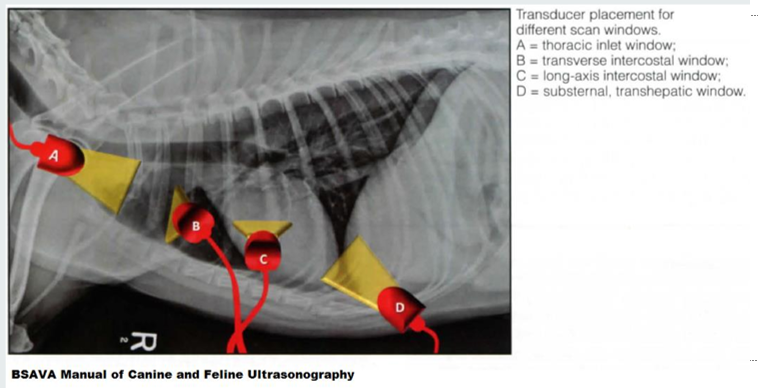

Thoracic U/S acoustic window.

A

thoracic inlet window

transverse intercostal window

long-axis intercostal window

substernal, transhepatic window